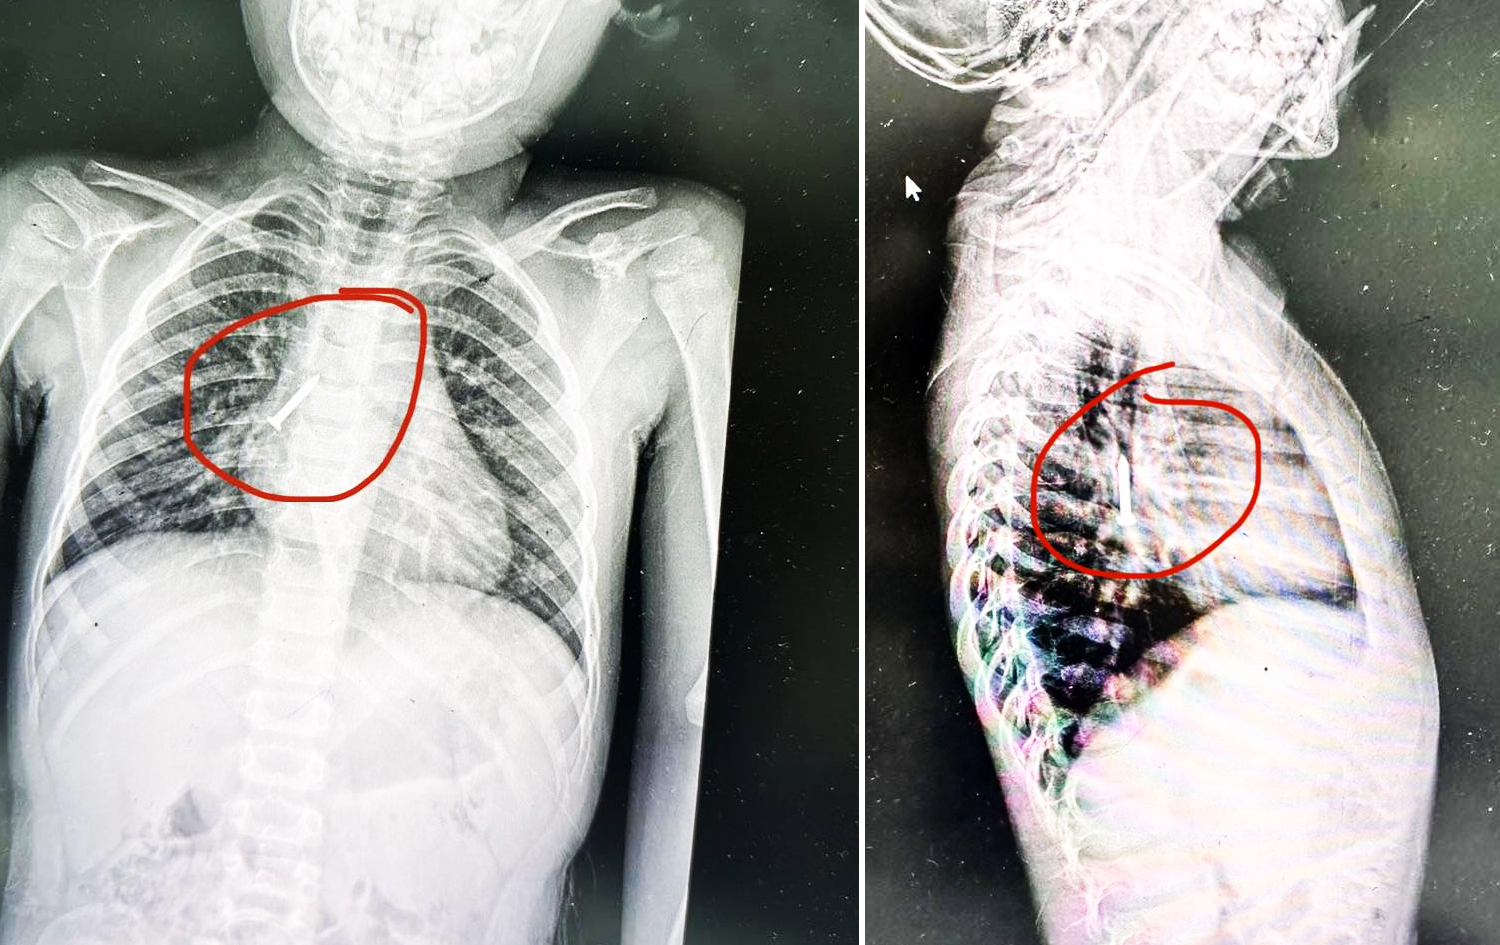

Dr. Enver, Rûdaw’a yaptığı açıklamada, çivinin çocuğun ana soluk borusunda hayati risk oluşturabilecek bir noktada bulunduğunu söyledi.

Çocuğun genel anestezi altına alındığını ve “bronkoskopi” yöntemiyle yabancı cismin başarıyla çıkarıldığını aktardı.